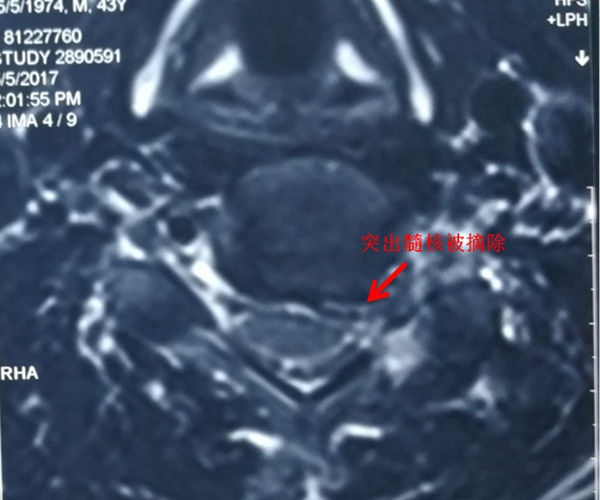

Key-hole手术后